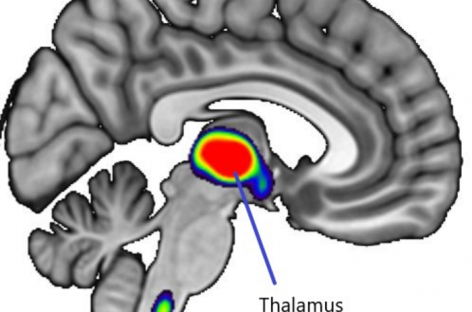

Tratamentele pentru depresie pot modifica structura creierului, au descoperit oamenii de ştiinţă 21 oct 2022